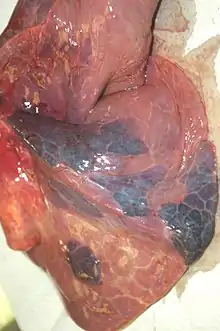

| Pulmonary infarcts found on autopsy | |